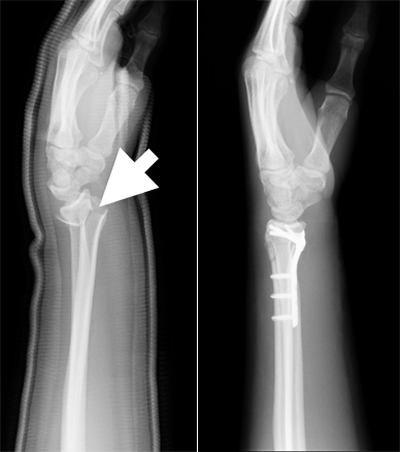

Prijelom radijusa nastaje na mjestu koje je 2-3 cm udaljeno od ručnog zgloba. Nastaje prilikom pada na ispruženu ruku gdje je ručni zglob u dorzalnoj fleksiji, a podlaktica u pronaciji. To je tzv. Collesova fraktura gdje je distalni fragment pomaknut prema dorzalno i radijus dobije izgled francuske vilice. Nasuprot ovom mehanizmu, pri padu na dorzum šake nastaje Smithova fraktura gdje je distalni fragment pomaknut prema volarno, oblik radijusa nalik je na bajonet.

U lokalnoj ili opštoj anesteziji se vrši manuelna repozicija, potom se stavlja longeta. Nakon 3 do 4 dana se ponavlja RTG i ako je položaj ulomaka dobar stavlja se cirkularni gips. Nekoliko dana nakon repozicije, podlaktica mora biti u uzdignutom položaju. Kod nestabilnih prijeloma i ukoliko se repozicijom ne postigne adekvatan položaj ulomaka, osovine i ako se ne riješi skraćenje, pristupa se operativnom zahvatu gdje se stavljaju vijci, male pločice ili Kirschnerove žice.